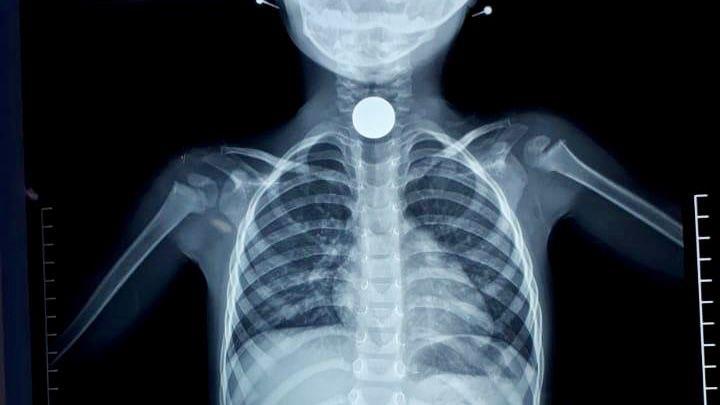

نجح فريق طبي بمستشفى طبرجل العام بمنطقة الجوف، في إنقاذ طفلة ابتلعت قطعة معدنية.

وأوضحت المديرية العامة للشؤون الصحية بالجوف، أن الطفلة تبلغ من العمر ثلاث سنوات، وابتلعت قطعة معدنية، ما أدى إلى سدّ مجرى الهواء.

وأبانت المديرية أن الفريق الطبي نجح في استخراج القطعة المعدنية من مجرى الهواء، فيما تم السماح بمغادرة الطفلة للمستشفى بعد التأكد من أنها بحالة صحية جيدة.